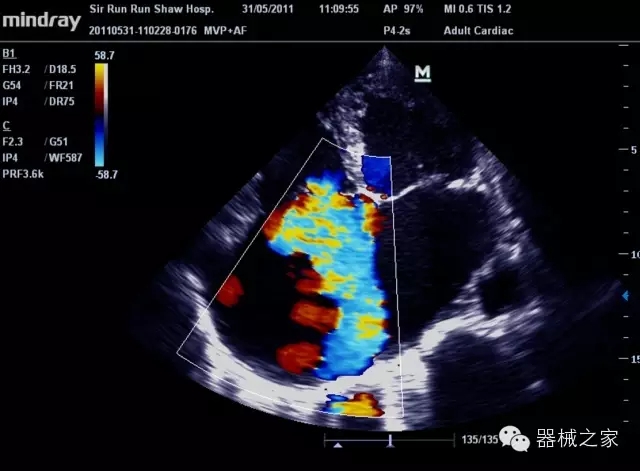

臨床圖片賞析

產(chǎn)品特點(diǎn)

·裝載有采用Multi-Core多核處理的非嵌入式平臺(tái),成像效率大大提高,并且能夠給用戶帶來(lái)高速、多任務(wù)并行信號(hào)處理體驗(yàn);

·優(yōu)秀的圖像效果、強(qiáng)大的功能體驗(yàn)、豐富的探頭選擇、合理的便攜式設(shè)計(jì),全中文顯示及病人管理界面,使得M7在任何場(chǎng)合、任何時(shí)候都能快速響應(yīng)更好的心血管、腹部、婦產(chǎn)、小器官等常規(guī)超聲檢查以及肌骨、神經(jīng)、顱腦、術(shù)中等新興領(lǐng)域的使用需求;

8倍波束并行處理系統(tǒng)

·在便攜式緊湊平臺(tái)上采用更多倍波束并行接收信號(hào)處理模式,無(wú)論二維還是彩色血流圖像狀態(tài)下,擁有更靈敏的回波頻移捕獲能力,大大提高時(shí)間分辨率,尤其使得心血管表現(xiàn)更為突出;

PSHI?寬帶頻移諧波技術(shù)

·在普通組織諧波的基礎(chǔ)上,通過(guò)精確控制的波束形成器,發(fā)射兩組具有相位偏差反向的信號(hào),并采用并行信號(hào)處理,數(shù)字化合成并采樣回波信號(hào),在高靈敏度的濾波器的處理過(guò)程中獲取更純凈的諧波信號(hào),使圖像具有更加出眾的細(xì)節(jié)分辨率;

iClear®+iBeam?

·智能化按線復(fù)合多角度獲取聲束的原始信號(hào),配合智能化的斑點(diǎn)噪聲識(shí)別及控制處理技術(shù),整體提高組織結(jié)構(gòu)細(xì)節(jié)分辨率,任何時(shí)候都能快速響應(yīng),更好的滿足心血管的使用需求;